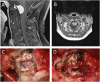

Background: Removal of anteriorly located tumors of the upper cervical spine and craniovertebral junction (CVJ) is a particular surgical challenge. Extensive approaches are associated with pain, restricted mobility of neck and head and, in case of foramen magnum and clivus tumors, with retraction of brainstem and cerebellum. Methods: Four symptomatic patients underwent resection of anteriorly located upper cervical and lower clivus meningiomas without laminotomy or craniotomy using a minimally invasive posterior approach. Distances of natural gaps between C0/C1, C1/C2, and C2/C3 were measured using preoperative CT scans and intraoperative lateral x-rays. Results: In all patients, safe and complete resection was conducted by the opening of the dura between C0/C1, C1/C2, and C2/C3, respectively. There were no surgical complications. Local pain was reported as very moderate by all patients and postoperative recovery was extremely fast. All tumors had a rather soft consistency, allowing mass reduction prior to removal of the tumor capsule and were well separable from lower cranial nerves and vascular structures. Conclusion: If tumor consistency is appropriate for careful mass reduction before removal of the tumor capsule and if tumor margins are not firmly attached to crucial structures, then upper cervical, foramen magnum, and lower clivus meningiomas can be safely and completely removed through natural gaps in the CVJ region. Both prerequisites usually become clear early during surgery. Thus, this tumor entity may be planned using this minimally invasive approach and may be extended if tumor consistency turns out to be less unfavorable for resection or if crucial structures cannot be easily separated from the tumor.